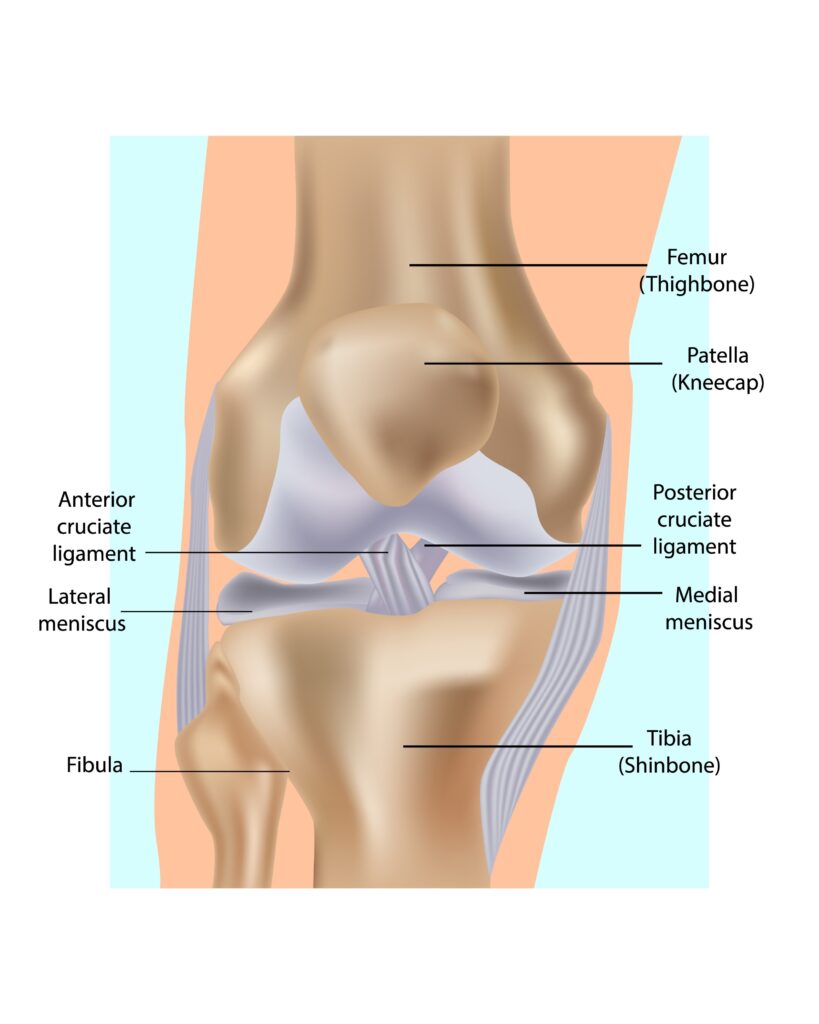

Think of your knee or shoulder like a complex machine. Sometimes, a small part inside breaks, like a wire (ligament) or a washer (meniscus).

1. ACL Reconstruction (Knee Ligament)

The ACL is crucial for stability. If it tears, your knee gives way. We fix it using the Internal Brace for maximum strength.

2. Meniscus Repair

The meniscus is your knee’s shock absorber. A tear causes sharp pain. We stitch it back together to save your natural cushion.

3. Shoulder Arthroscopy

Suffering from a frozen shoulder, dislocation, or rotator cuff tear? We fix these permanently so you can lift your arm pain-free.

4. PCL & Multi-Ligament Surgery

For severe injuries (like bike accidents common in Mumbai traffic), Dr. Bora is an expert in complex multi-ligament restoration.